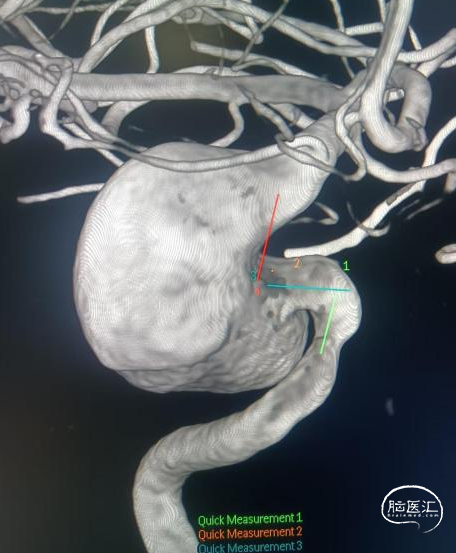

术前影像

脑动脉DSA提示右侧颈内动脉虹吸段巨大动脉瘤。

右侧虹吸段载瘤动脉近端直径为4.13mm,瘤体最宽径为24.2mm,动脉瘤流入、流出道均显示明显迂曲,近端载瘤动脉也有迂曲。病变范围约32mm。

术前讨论

· 术前诊断:右侧颈内动脉虹吸段巨大动脉瘤。

· 手术预案:巨大动脉瘤,且载瘤动脉远近端血管较迂曲,采用单枚70mm长Repath®血流导向密网支架置入术。